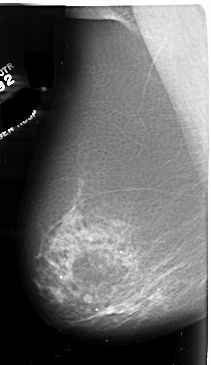

A_1008_1.LEFT_MLO

LEFT_MLO LINES 6556 PIXELS_PER_LINE 3796 BITS_PER_PIXEL 16 RESOLUTION 42 NON_OVERLAY